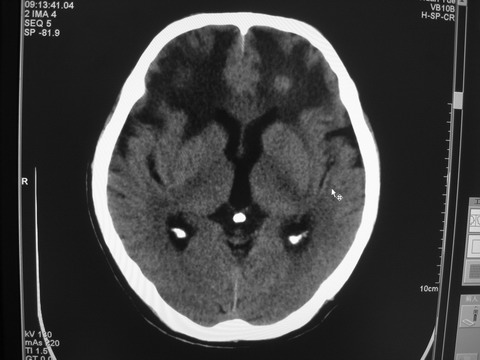

患者 男 69岁 头晕头痛不适

多发病灶,指状水肿,首先诊断转移瘤。

多个结节并周围大面积水肿区,多考虑多发性脑转移瘤

小病灶、大水肿,病灶多发,首先考虑多发转移瘤;建议查原发灶。

额顶叶多发小病灶、大水肿,首先考虑多发转移瘤;建议查原发灶

脑内多发病灶,小病灶,大水肿。

典型转移性肿瘤。

应进一步检查,查找原发病灶。

结果 : 该患者结肠癌病史5年 考虑脑转移